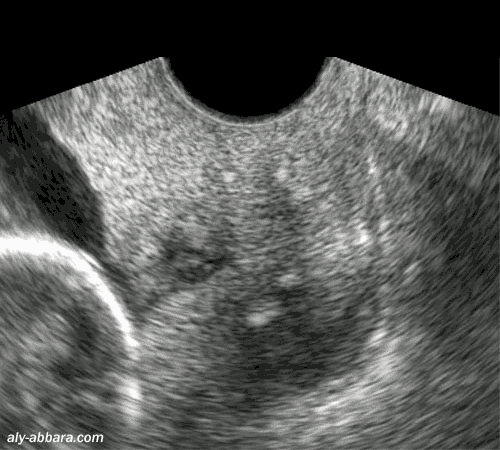

Coupe sagittale passant par le col utérin à 16 semaines d'aménorrhée et récemment cerclé

Il s'agit au départ d'un col court (25 mm de longueur) avec orifice interne béant, sous forme d'un entonnoir.

On peut remarquer les modifications apportées par le cerclage du col utérin

: la longueur du col est augmentée,

avec une portion sécurisée du canal cervical de 20 mm, mais l'orifice interne du col reste toujours béant

Incompétence cervico-isthmique (béance de l'orifice interne du col utérin)